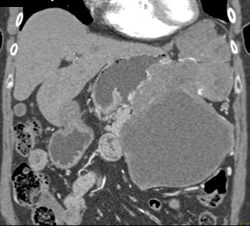

GIST Tumor